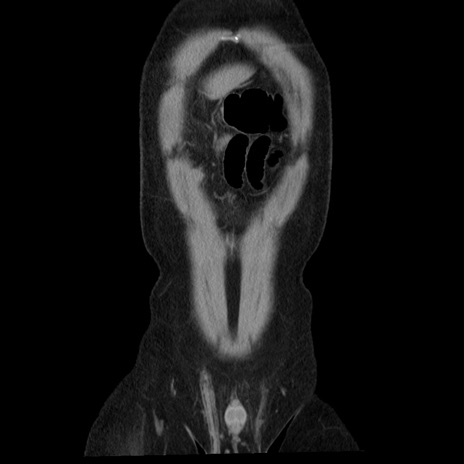

横断像